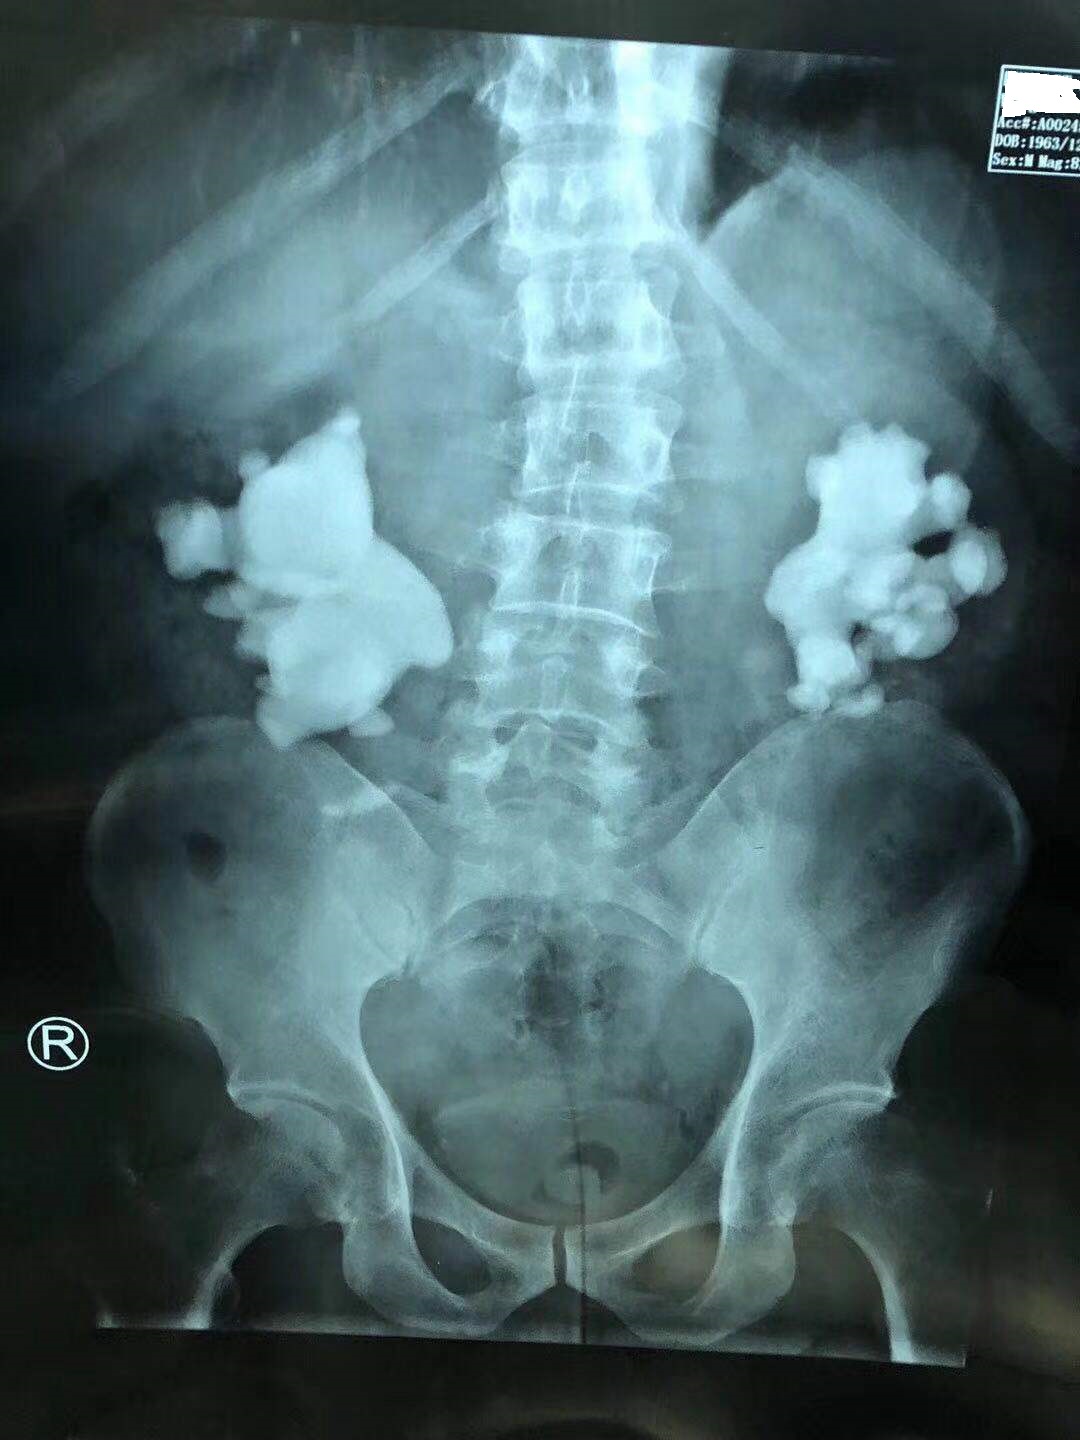

林先生的双肾鹿角形结石

第一次手术取净右肾结石!